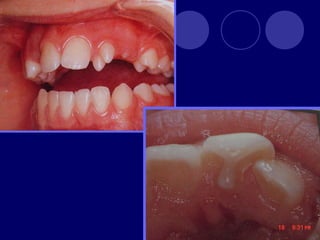

SUPERNUMERARIOS  :aumento enel numero de dientes.

 Temporal: 0.5% Permanente: 3%  Maxilar  Masculino  Únicos  Múltiples: Sx. Gardner, disostosis cleidocraneal

ANOMALÍAS DE TAMAÑO MACRODONCIA:  Generalizada verdadera  Generalizada relativa  De un solo diente

 MICRODONCIA:  Generalizada verdadera Generalizada relativa  De un solo diente

FUSIÓN: unión dedos gérmenes (esmalte,dentina),dos cámaras pulpares, más frecuente en la dentición temporal GEMINACIÓN: tentativa fallida de un germen a dividirse (diente con dos coronas y una sola raíz, un solo conducto)